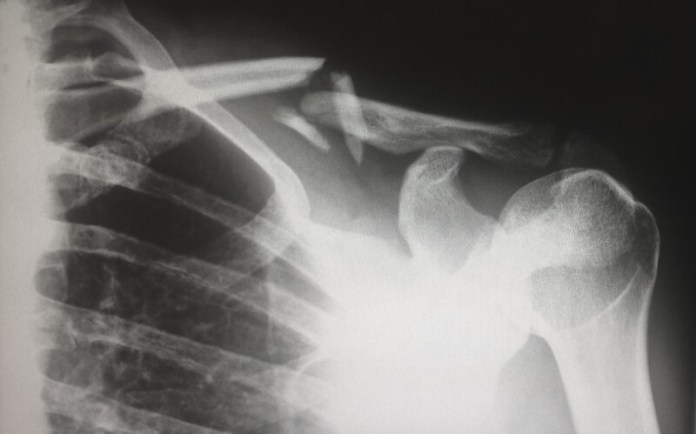

Pneumothorax, which is the existence of gas within the pleural space that appears between the chest wall and the lung, is still a huge health problem globally with massive associated healthcare and morbidity costs.

Without fast management, the condition can cause a complete collapse of the lungs and other potentially lethal complications.

Pneumothorax can either be spontaneous or be triggered by underlying complications, trauma, and lung disease from surgical procedures or biopsies.

With an incidence rate of approximately 18 to 28 cases for a population size of 100,000, there are between 130,000 and 207,000 pneumothorax cases in Europe each year.

Late-diagnosis or misdiagnosis of pneumothorax affects nearly 74,000 Americans annually.